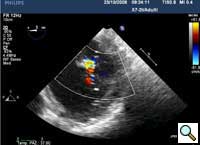

Figure 7

In absence of controlled clinical trial data which are forthcoming from the EVEREST II randomized study, the indications for the MitraClip therapy are currently based on registry experience and will evolve as the technique improves, experience is growing and the data to demonstrate efficacy and safety becomes available. At this time, the best indication for the MitraClip therapy is for symptomatic patients with clinically significant functional or degenerative MR who are at high or increased risk for open heart surgery. From a pure technical standpoint, the procedure so far has only been demonstrated in a subgroup of patients with specific anatomical characteristics which are summarized below and shown in Figure 3. Anatomic suitability is assessed by transesophageal echocardiography, and mitral regurgitation should originate from the central portion of the valve involving the A2-P2 segments, since the device is not ideal to work in the commissures at this time; the mechanism of MR can be either a prolapse/flail or MR due to restricted leaflet motion unrelated to rheumatic disease; the separation between the two leaflets at the site of regurgitation should be limited; severe annular dilatation and/or severe calcification should be absent or is relevant. In case of flail, the flail segment width should be less than 15 mm, and the flail gap less than 10 mm. Figure 4 is a 3D echo image of a patient with posterior leaflet prolapse selected for MitraClip therapy. In case of functional MR, the leaflets should have a minimal residual tissue available for coaptation with the MitraClip device. Figure 5 shows 2D color Doppler jet extension over the coaptation line at TEE short axis transgastric view, while Figure 6 shows the tenting area and the coaptation depth of a patient undergoing MitraClip implant.